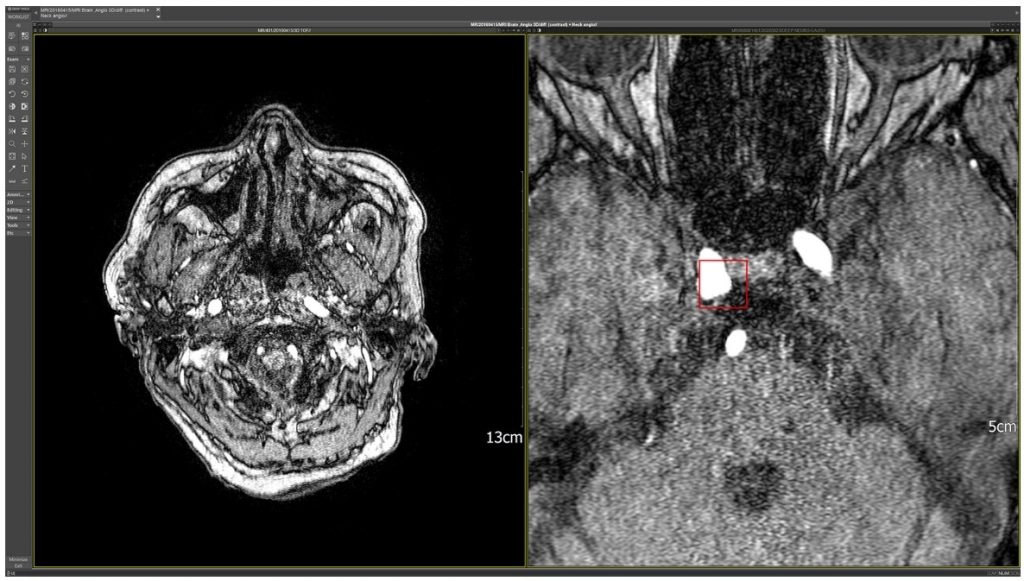

마지막은 의료 AI이다. 다른 의료 AI 기업들과 마찬가지로 엑스레이, CT, MRA 등의 의료 영상 이미지를 인공지능이 분석해 여러 가지 질병을 알려주는 솔루션이다. 국내 최초로 뇌혈관질환 진단 솔루션인 DEEP:NEURO(이하 딥뉴로)가 혁신 의료기술로 선정된 후 보건복지부의 고시 발령에 따라 이달부터 병원에서 환자에게 활용이 가능하게 됐다. 의료 AI는 그동안은 성장에 대한 기대감으로 주가가 올랐지만, 하반기부터 비급여 진료를 받을 수 있게 되면서 병원으로부터 실제로 매출이 발생하는 상황이 됐다. 이제는 실적으로 보여줄 수 있는 것이다.

딥노이드의 딥뉴로는 뇌동맥류의 부피나 뒤틀어짐 등을 체크해 뇌경색 등을 방지할 수 있도록 해주는 솔루션이다. MRA 영상을 기반으로 딥러닝된 솔루션이기 때문에 다른 업체들의 폐CT, 뇌MRI, 가슴 엑스레이의 솔루션과 경쟁할 필요가 없다. SK증권에 따르면 뇌동맥류 환자는 2022년 기준 국내 117만명이다. 환자 입장에서는 비급여 처방이 가능하기 때문에 진료비의 부담이 없고, 병원 입장에서는 추가 수입이 생기기 때문에 적극적인 처방이 예상된다. 뇌동맥류를 진단하는 뇌MRA에 대한 솔루션은 동사가 유일하기 때문에 내년부터 의료부문에서도 실적 기여가 예상된다.